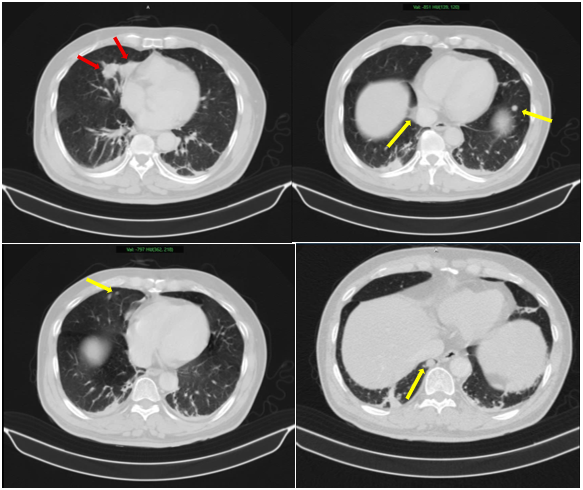

Sau đó, bệnh nhân được chụp PET/CT toàn thân, một phương pháp y học hạt nhân hiện đại, rất có giá trị trong phát hiện các tổn thương, đặc biệt là các tổn thương di căn hạch và di căn xa. Phim chụp cho thấy bệnh nhân có rất nhiều tổn thương tại nhu mô phổi hai bên, tại tuyến thượng thận trái, tại xương nhiều vị trí và tại tuyến tiền liệt, tăng hấp thu FDG thể hiện tính chất ác tính (Hình 5).

Hình 5: Hình ảnh PET/CT cho thấy: 02 khối u phổi phải, kích thước lớn nhất 16 x 23 mm, xâm lấn vào trung thất (SUVmax: 17,8) và các nốt đặc nhỏ rải rác nhu mô hai phổi, tăng hấp thu FDG (SUV: 10,5) (mũi tên đỏ). Hình ảnh các tổn thương tại xương (mũi tên trắng) tương ứng với các vị trí tổn thương quan sát thấy trên xạ hình xương (SUVmax: 22,2). Hình ảnh nốt tuyến thượng thận trái(mũi tên xanh), tăng hấp thu FDG (SUVmax: 15,2). Hình ảnh tăng hấp thu FDG tại vùng chuyển tiếp,vùng ngoại vi bên phải tuyến tiền liệt và thành dưới bàng quang (SUVmax: 17,1) (mũi tên vàng).